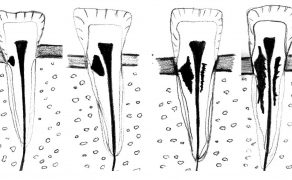

STRESZCZENIE: Endodoncja to dziedzina stomatologii stanowiąca każdego dnia wyzwanie dla wielu stomatologów. Aby efekt końcowy leczenia okazał się sukcesem, potrzebne będą narzędzia i metody, które pozwolą go osiągnąć. Nowoczesna endodoncja posiłkuje się wieloma etapami pracy, przyrządami i narzędziami. Dlatego niezwykle istotne jest również doświadczenie kliniczne i wyczucie stomatologa. Wybór mogą znacznie ułatwić narzędzia, które pozwalają na minimalnie inwazyjną, ale również maksymalnie skuteczną pracę w kanale. Materiałem, z którego powinny być wykonane takie narzędzia, jest stop niklowo-tytanowy (Ni-Ti). Przykładem może być np. ZenFlex firmy Kerr. Metoda opracowania kanałów korzeniowych powinna być dobrana indywidulnie do zęba pacjenta. Morfologia systemów kanałowych bywa bardzo różnorodna, a istnieją również miejsca konieczne do oczyszczenia, do których nie docierają narzędzia. Dzięki dobraniu odpowiednich substancji płuczących możliwe jest ich właściwe oczyszczenie. Jako przykład przedstawione zostały dwa przypadki kliniczne leczenia zęba 21 oraz 16.